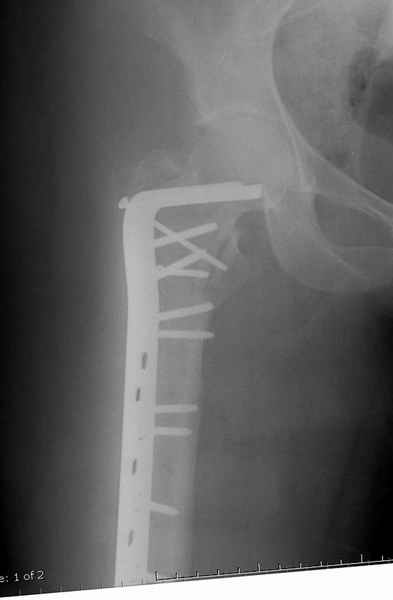

Для молодых больных выбрал бы тактику fixed angled device 95 degree Blade Plate, техника непрямого метода репозиции, который описал в своей книге Jeff Mast, Planning and Reduction Technique in Fracture Surgery ( method of Inderect Reduction), репозиция и фиксация происходит за счет фиксации головки бедра к femoral shaft с помощью пластины, а что в середине должны репонироваться без больших усилии и без разрушения мягкотканого соединения c медиальной стороны.

Пластина дает свободу:

Valgus-varus; extention- flexion, зависит только от образования канала для blade на головке.

Ap pelvis Rt sub-intra trochanteric Fracture, AP Rt hip, Postop Blade Fixation